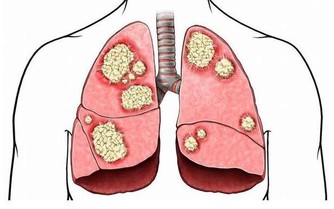

不僅咳嗽,還有胸悶、痰中帶血的情況,可能是心臟和肺部出現嚴重問題,常常因為咳嗽不能安穩入睡,家長要重視起來。

家長要留心孩子的心肺功能,若是發現孩子最近一段時間總是清嗓子,不喜歡外出運動,體力下降了,可能是肺功能降低了,建議進一步到醫院確診。